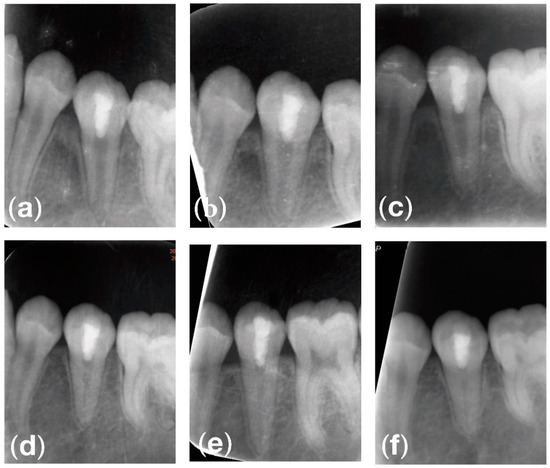

2. Case Report

2.2. Clinical Exams and Diagnosis

3. Results